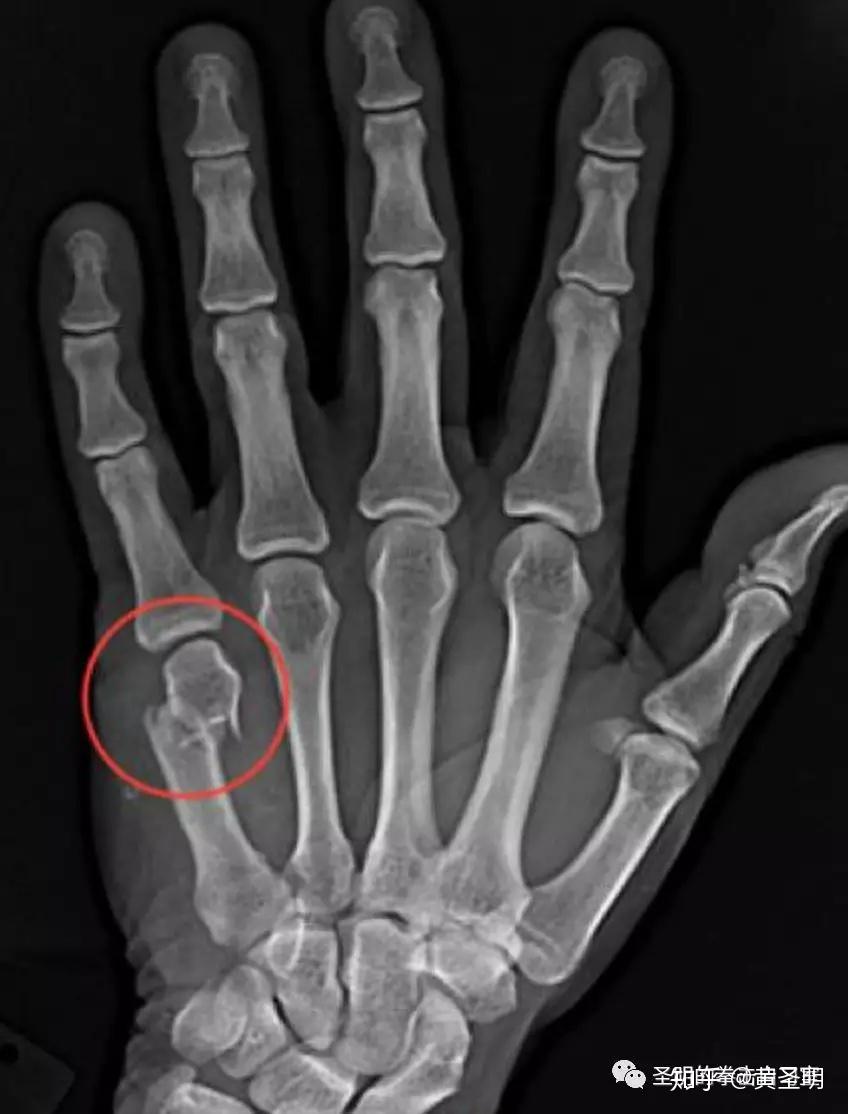

From zhuanlan.zhihu.com

拳击运动腕关节的损伤及康复 知乎 Playing Sports With Broken Finger what they do want is to help your body completely heal so you can return to playing the. Since the hands are frequently used, they are at higher risk. broken fingers are common injuries and they can happen due to a fall while playing sports, fingers getting caught in car doors, bending your finger in an awkward position,. Playing Sports With Broken Finger.